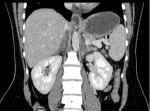

Diagnostic assessment: initial abdominal ultrasound excluded surgical emergencies such as acute appendicitis, cholecystitis, or placental abruption. Urinalysis showed leukocyturia (20 cells/field) and hematuria (10 cells/field) without visible microorganisms; subsequent urine culture remained negative. Based on fever, lumbar tenderness, and leukocyturia, a diagnosis of acute pyelonephritis was suspected, and empirical cefotaxime was initiated. However, the lack of clinical improvement after 48 hours, persistent fever, intractable vomiting, and onset of tachypnea (46 breaths/min) prompted diagnostic reconsideration. Laboratory investigations demonstrated a marked inflammatory response (C-reactive protein 266 mg/L). Arterial blood gas analysis revealed metabolic acidosis (pH 7.33, PaCO2 11 mmHg, HCO3- 11 mmol/L) without hyperlactatemia (lactate 1.6 mmol/L). Serum electrolytes showed hyponatremia (129 mmol/L) and hypokalemia (3.2 mmol/L), with preserved renal function. Given the acute tachypnea, pulmonary embolism was suspected, and CT pulmonary angiography was performed, excluding this diagnosis. Alternative diagnoses were systematically considered and ruled out, including appendicitis, cholecystitis, pancreatitis, renal infarction, adrenal hemorrhage, Hemolysis elevated liver enzymes and low platelets (HELLP) syndrome, and acute fatty liver of pregnancy. Because magnetic resonance imaging (MRI) was not emergently available at our institution and given the persistence of unexplained symptoms, contrast-enhanced abdominal CT was performed, revealing bilateral adrenal enlargement without contrast enhancement (Figure 1, Figure 2). Both adrenal glands appeared enlarged with no parenchymal enhancement after intravenous contrast administration, consistent with adrenal ischemia and infarction. The coronal reconstruction confirmed the bilateral and symmetrical nature of adrenal involvement. Dotted lines on imaging highlighted the non-enhancing adrenal glands. Endocrine evaluation showed a serum cortisol level of 128.2 nmol/L, which is below the threshold suggestive of adrenal insufficiency in critically ill patients according to current guidelines. Adrenocorticotropic hormone (ACTH) measurement and dynamic testing were not immediately available and were not performed to avoid delaying urgent treatment.

Figure 2: coronal view of contrast-enhanced abdominopelvic computed tomography showing bilateral adrenal gland enlargement with non-enhancing areas in a 34-week pregnant patient